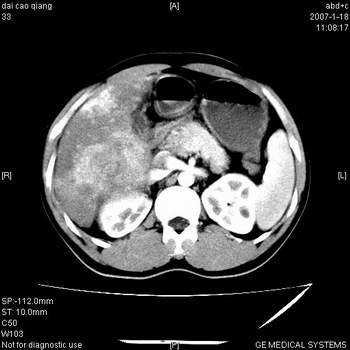

肝右叶巨块型肝癌,伴癌栓形成.

符合巨块型肝癌表现:

1、平扫低密度,增强后表现为快进快出。

2、动脉期可见迂曲的动脉供血血管

3、并可见门静脉右支癌栓形成

4、可见假包膜

5、腹主动脉旁结节影,考虑肿大淋巴结。

肝右叶巨大不均匀低密度肿块,前缘有假包膜,增强明显的呈快进快出表现,门脉右支有癌栓,病人虽然年轻但还是首先考虑肝右叶巨块形肝癌,病人血象高只能说有合并感染。不支持肝脓肿。

巨块型肝癌并门静脉右支癌栓